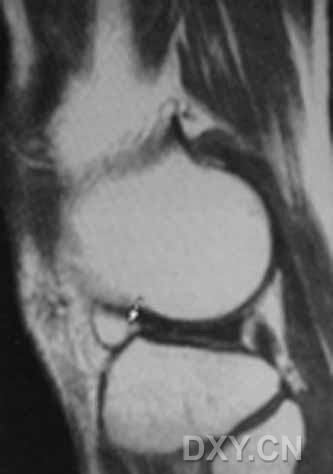

| 盘状半月板

3 半月板Ⅲ级损伤即撕裂,在MRI的T2WI上表现为半月板内的高信号影达到关节面缘。半月板撕裂表现复杂,正确判断半月板撕裂的部位、形态、类型对于临床手术方案的制定非常重要。根据MRI信号及半月板形态改变半月板撕裂又可以分为6个类型: 3.1 水平撕裂:MRI上表现为与胫骨平台平行的条状高信号影,此种类型比较少见。 3.2 垂直撕裂:MRI上表现为半月板内条状高信号影与胫骨平台垂直。 3.3 斜行撕裂:MRI上半月板内条状高信号影的方向与胫骨平台成一定的角度,矢状面上条状高信号影达到关节面的上缘或下缘,有时不易与纵形撕裂区别,需要结合冠状面或三维图像。此型是最常见的类型。 3.4 放射状撕裂:MRI上半月板内条状高信号影的方向与半月板的长轴垂直,好发生于内侧半月板的内1/3处,比较少见。 3.5 纵形撕裂:MRI上半月板内高信号影与半月板的长轴方向平行,此型撕裂累及半月板的范围广,可进展为桶柄状撕裂。 3.6 桶柄状撕裂:桶柄状撕裂几乎累及半月板的所有部位,临床症状重,关节绞索明显,为半月板撕裂的一个特殊而严重的类型,多来源于纵形撕裂,是半月板后角发生纵行撕裂后经体部向前角延伸,其内侧片段发生移位,这移位的片段类似于桶的柄,此类型撕裂在MRI中常易漏诊,可见内移的半月板碎片位于髁间窝、交叉韧带旁,矢状面上可以出现双前交叉韧带征或双后交叉韧带征,双半月板前角或双半月板后角征,以及领结缺如征。在MRI正中矢状位像上半月板桶柄状撕裂内移的半月板碎片移至后交叉韧带前下方,呈弯曲条状低信号,形似后交叉韧带,与正常的后交叉韧带一起构成“双后交叉韧带征”,这一征象在诊断半月板桶柄状撕裂中有重要意义。双后交叉韧带征常伴有半月板后角及体部的体积缩小。领结缺如征对诊断桶柄状撕裂有高的敏感性和特异性,比双交叉韧带征敏感,正常矢状位应连续2个层面出现领结征,如果只显示1层或无此征称为领结缺如征。另有鹦鹉嘴样撕裂、半月板关节囊分离等,少见。 4 盘状半月板:是半月板异常增大增厚,因其形态不利于膝关节负荷的传导,压力往往集中于较小的面积上,故易损伤。临床上表现为弹响、活动受限,合并撕裂时出现疼痛、腿无力,关节绞索。MRI上表现为:矢状面上若以5mm层厚扫描时有3个或以上层面显示半月板前后角相连,形成蝴蝶结样改变,冠状面上半月板最窄处宽度大于14~15mm,外侧缘高于对侧2mm以上。盘状半月板外侧多见。